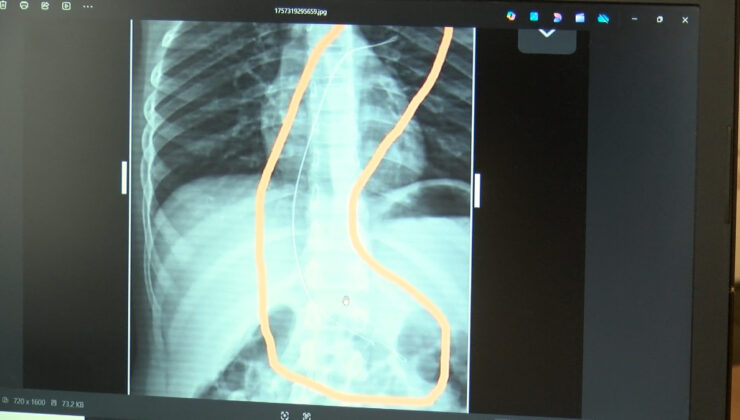

Burada çekilen röntgen ve MR’da Aram’ın vücudunda kateter unutulduğu görüldü.

Bunu takarken büyük bir ihmalkarlık yapılarak vücudunda unutuldu. Mayıs ayında müvekkilim çok öksürdüğü için Şırnak Devlet Hastanesi’ne kaldırıldı. Burada yapılan tetkiklerde kateterin unutulduğu tespit edildi.

Bu kateterin vücutta yol aldığı tespit edildi. İlk giriş yeri ve çıkarıldığı yer arasında çok fark var ve kalp kapakçığı ile ciğerlerine zarar verdiği tespit edildi.

Röntgeni ve MR’ı çekildi. Tuhaf bir şey olduğunu anladık. Doktor röntgeni gösterdi. Tel kalmıştı. Çok kötü bir şekilde. Acil doktoru film çektikten sonra bize bir tel parçasını gösterdi. Bizi bekletmeden Diyarbakır’a sevkimizi verdiler. Diyarbakır Gazi Yaşargil Eğitim ve Araştırma Hastanesi Kadın Doğum ve Çocuk Ek Binası’na gittik.